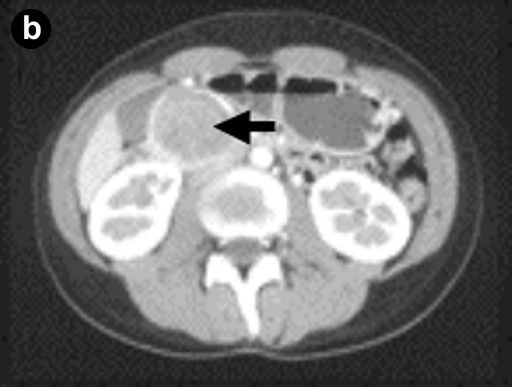

A 26-year-old woman, who had complained of intermittent abdominal pain for 8 years, was referred to our hospital for further evaluation of a pancreatic tumor. She was 159 cm tall and weighed 48 kg. Her pulse rate was 70 min-1 and her blood pressure was 120/80 mmHg. There was no evidence of jaundice. The abdomen was flat and soft but tenderness was present at the upper abdomen. The tumor was not palpable. Other physical examinations were unremarkable. Laboratory data including hematology, blood chemistry including amylase and lipase, and tumor markers including CEA and CA 19-9 were within the reference limits. US imaging showed a pancreatic tumor with solid and cystic components (Figure 1a). A CT scan demonstrated that the well-circumscribed tumor was located in the pancreatic head (Figure 1b). Pancreatograms obtained by MRI and ERCP showed no communication between the tumor and the pancreatic duct. In addition, the ventral pancreatic duct did not communicate with the dorsal pancreatic duct (Figure 2ab). Duodenum-preserving pancreatic head resection was performed [7, 8]. Briefly, the subtotal pancreatic head was resected preserving the bile duct. Reconstitution with drainage of the pancreatic secretion from the remnant pancreas took place with Roux-en Y end-to-side pancreaticojejunostomy. The resected tumor was 50x45x52 mm in size and 50 g in weight, accompanied by hemorrhagic degeneration and surrounded by a red fibrotic pseudocapsule (Figure 3a). Microscopically, the tumor had a cystic component (Figure 3b). The tumor cells were small to intermediate in size with faintly eosinophilic cytoplasm. The nuclei had slight indentations and no mitosis (Figure 3c). Immunohistochemical examination demonstrated that the tumor cells were positive for the progesterone receptor (Figure 3d). In addition, the tumor cells were also stained with alpha-1-antitrypsine and vimentin but not with estrogen receptors, NSE, insulin or glucagon (data not shown).

Figure 1. a. Abdominal US. The tumor has solid (arrow) and cystic components (arrowhead). b. CT scan. The tumor is well encapsulated with peripheral enhancement (arrow). |